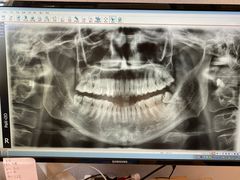

• 赫尔森口腔·牙齿种植修复

• -赫尔森口腔·牙齿种植修复